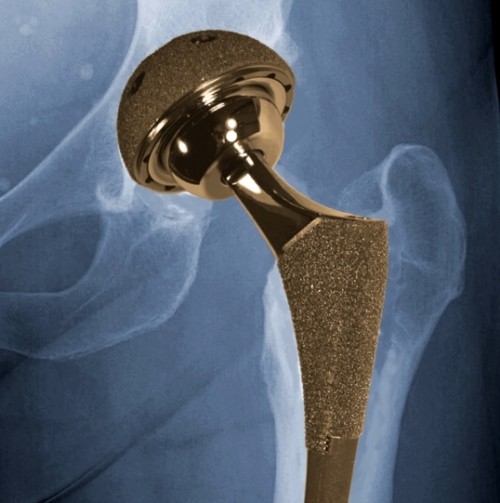

Me përvojën e tij 30-vjeçare në fushën e mjekësisë dhe 23-vjeçare në fushën e kirurgjisë ortopedike, ai është i përqendruar në artroplastikën totale të artikulacioneve (koksofemoral, gjurit, kyçit të këmbës, shpatullës, bërrylit, kyçit të dorës dhe artikulacioneve të vogla). Dhe ka një numër të madh suksesesh në rastet që kanë kryer protezim total të artikulacionit koksofemoral displazik dhe të dislokuar.

Në fokus të veprimtarisë ortopedike të klinikës Albaturk Medical Consulting krahas ndërhyrjeve të ndryshme kirurgjikale ortopedike janë kirurgjia protezike e gjurit dhe ajo e artikulacionit koksofemoral me një qëndrueshmëri dhe jetëgjatësi të madhe të protezës dhe kosto ekonomike të arsyeshme.

- protezimi i artikulacionit koksofemoral